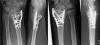

Figure 1.

AP and lateral radiographs in two cases of distal radial fracture operated with the TriMed system. A. This patient was operated using a radial pin-plate and a volar buttress pin. Additional stability was achieved using Norian SRS bone substitute. B. In intraarticular fractures with an ulnar fragment, an ulnar pin-plate could be combined with the radial pin-plate.